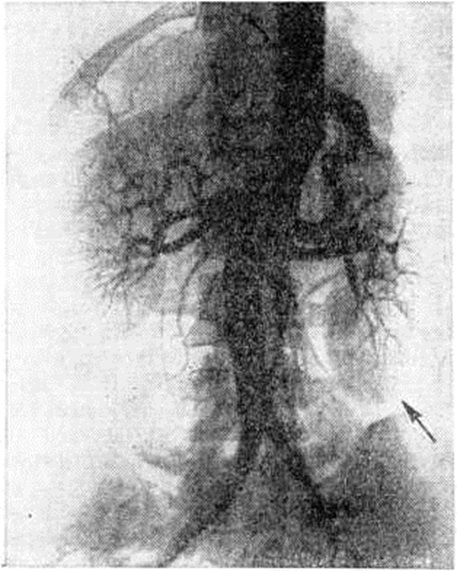

Опущение почек (нефроптоз) обычно устанавливают уже при обзорной рентгенографии (томографии) забрюшинного пространства. Характер нефроптоза и состояние почек уточняют с помощью контрастного исследования чашечно-лоханочной системы и мочеточников (выделительная или ретроградная урография). По клинические, показаниям производят исследование сосудов почек (рисунок 4), радиоизотопное исследование (смотри полный свод знаний) или компьютерную томографию (смотри полный свод знаний: Нефроптоз). Нефроптоз дифференцируют с врождённой дистопией почки, для которой характерны низкое расположение ночки и короткий мочеточник, лишенный изгибов, свойственных нефроптозу. При компьютерной томографии нередко отмечается значительное уменьшение паранефральной жировой клетчатки, способствующее опущению почки (смотри полный свод знаний: Томография компьютерная).